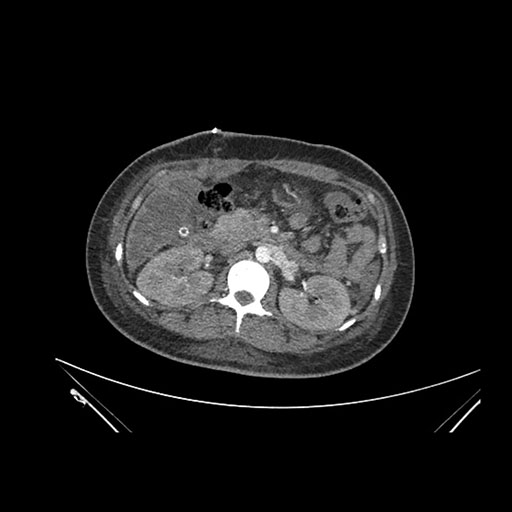

Imaging Analysis

Look through the patient's CT scan to identify any areas of concern for the necessary procedure.

Axial Arterial